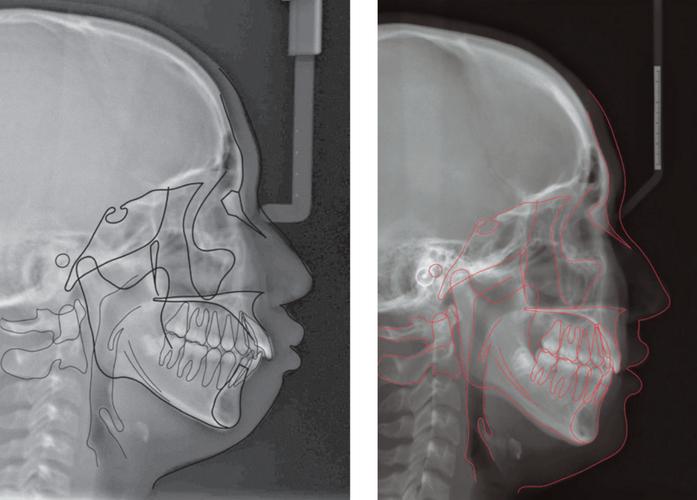

头颅侧位片的定位依赖于三个关键解剖点,它们共同定义了头颅的正中矢状面(Mid-sagittal Plane)和颅底平面(Cranial Base Plane):

- 鼻根点(Nasion, N): 鼻梁最凹陷点(鼻额缝中点)。

- 蝶鞍点(Sella, S): 蝶鞍的中心点(通常在侧位片上可见)。

- 耳点(Porion, Po): 外耳道最上点(外耳道穹窿顶)。

- 正中矢状面垂直于地面: 患者的头颅必须被摆放在一个位置,使得通过鼻根点(N)和蝶鞍点(S)的连线(NS线)与地面垂直,这意味着患者的头颅左右两侧完全对称地位于X光束中。

- 眶点(Orbitale, Or)与耳点(Po)水平对齐: 在侧位片上,眶点(Or,眼眶最下点)和耳点(Po)应位于同一水平线上,这确保了颅底平面(Frankfort Horizontal Plane, FH平面)在影像中是水平的。

- 鼻根点(N)、蝶鞍点(S)、耳点(Po)、眶点(Or)是否清晰可见?

- 眶点(Or)和耳点(Po)是否在同一水平线上?(这是判断FH平面是否水平的关键)

- 头颅左右两侧是否对称?下颌骨升支、髁突、颧弓等结构是否双侧对称显示?